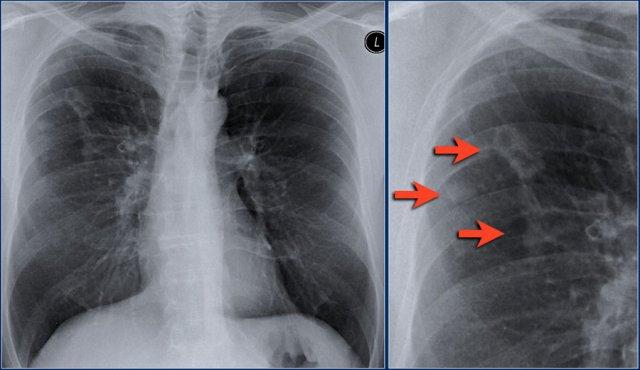

Xẹp thùy giữa phổi phải

Hãy quan sát kỹ các hình X-quang trước, sau đó tiếp tục đọc.

Các dấu hiệu là gì?

- Xóa mờ bờ tim phải (dấu hiệu bóng mờ)

- Đám mờ hình tam giác trên phim nghiêng do xẹp thùy giữa

Thông thường, xẹp thùy giữa phổi phải không gây nâng cao cơ hoành phải đáng kể.

Ngực lõm (pectus excavatum) có thể bắt chước hình ảnh xẹp thùy giữa trên phim thẳng, nhưng phim nghiêng sẽ giúp phân biệt được vấn đề này.